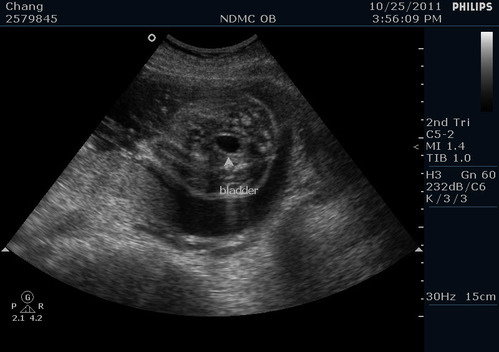

膀胱~醫生說裡面有尿尿~表示腎臟功能正常喔